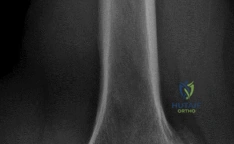

A 68-year-old male presents with chronic, severe right shoulder pain and pseudoparalysis (inability to actively elevate the arm), despite extensive physical therapy and injections. MRI reveals a massive, retracted, irreparable posterosuperior rotator cuff tear with significant fatty infiltration (Goutallier Stage 3-4) of the supraspinatus and infraspinatus. Glenohumeral arthritis is mild (Samilson-Prieto Grade 1).

Option D (Reverse total shoulder arthroplasty - rTSA) is the most appropriate treatment for this patient. The rTSA design medializes the center of rotation and increases the deltoid lever arm, allowing the deltoid to effectively elevate and abduct the arm, thereby compensating for the irreparable rotator cuff deficiency and addressing the pseudoparalysis. It reliably provides pain relief and functional improvement in this specific scenario, even with mild glenohumeral arthritis. The image provided shows superior migration and possible acromial erosion, which are common findings in rotator cuff arthropathy, reinforcing the choice of rTSA.